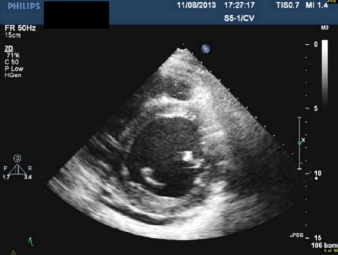

3. 82歲老婦人到院主訴五天來有日趨嚴重的呼吸困難。病史顯示30年前就有醫師告知心臟雜音,因無症狀,未曾有任何治療。近五年來運動耐受逐漸不佳,且偶有突發性悸動及心絞痛,特別在步行樓梯間更加惡化。住院當日清晨3點突然重度呼吸困難,因而急診住院。理學檢查:血壓110/62 mmHg;心跳90/分;頸靜脈怒張。心臟大小正常,但在右上胸骨緣及心尖部有Gr III/VI systolic murmur, S2減輕:其他所見尚無異常。其胸部X光、心臟超音波及心電圖如圖。WBC,5.2 k/micro L;AST,21U/L;CK,111U/L;CK-MB,14.6U/L;Troponin I,0.06 ng/ml。請問下列何項處置最恰當? (A) Percutaneous coronary intervention (B) Aortic valve replacement (C) Nitroglycerin IV infusion at the rate of 15mcg/min (D) Titrate PO carvedilol starting from 3.125 mg and reassess in 3 months (E) Treating with IV digoxin 0.125mg in conjunction with IV bolus Furosemide 20mg and then 20 mg BID

超音波

Estimated aortic valve area = 0.37 cm2 With the peak Ao flow at 580 cm/sec ; the peak pressure gradient at 134mmHg and the LVEF (56%)